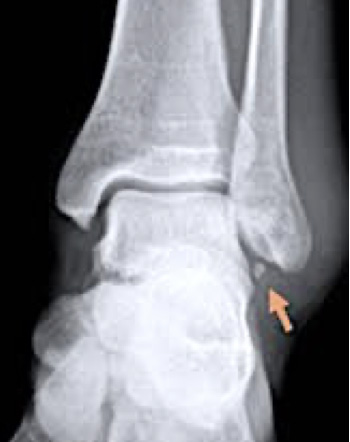

La radiografía simple no se realiza de forma sistemática, sólo en casos de esguinces graves, sospechas de fracturas asociadas o en esguinces de mala evolución. Con frecuencia se aprecia una pequeña avulsión de la inserción del LLE en la punta del peroné, que no debemos considerar como una fractura sino como un arrancamiento del ligamento cuyo tratamiento será casi similar al de cualquier esguince.